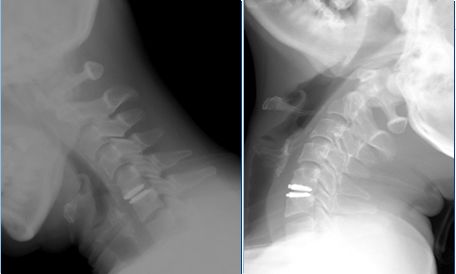

典型案例

黄某,女,39岁,颈痛伴左上肢放射痛及麻木感1年,诊断为神经根型颈椎病。行颈5-6椎间盘切除减压、人工椎间盘置换术。

术前X线、CT、MRI提示颈5-6椎间盘右后型突出并神经根受压。

颈5-6人工椎间盘置换术后,颈椎手术节段运动可以继续保留。

微创前路颈椎椎间盘切除减压融合固定术后,切口仅需4厘米,出血约50-100毫升,术后脊髓压迫彻底解除。